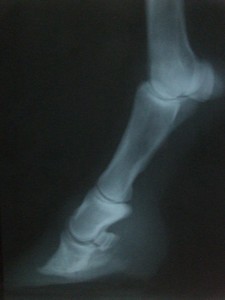

Pravá přední 19.3.20009